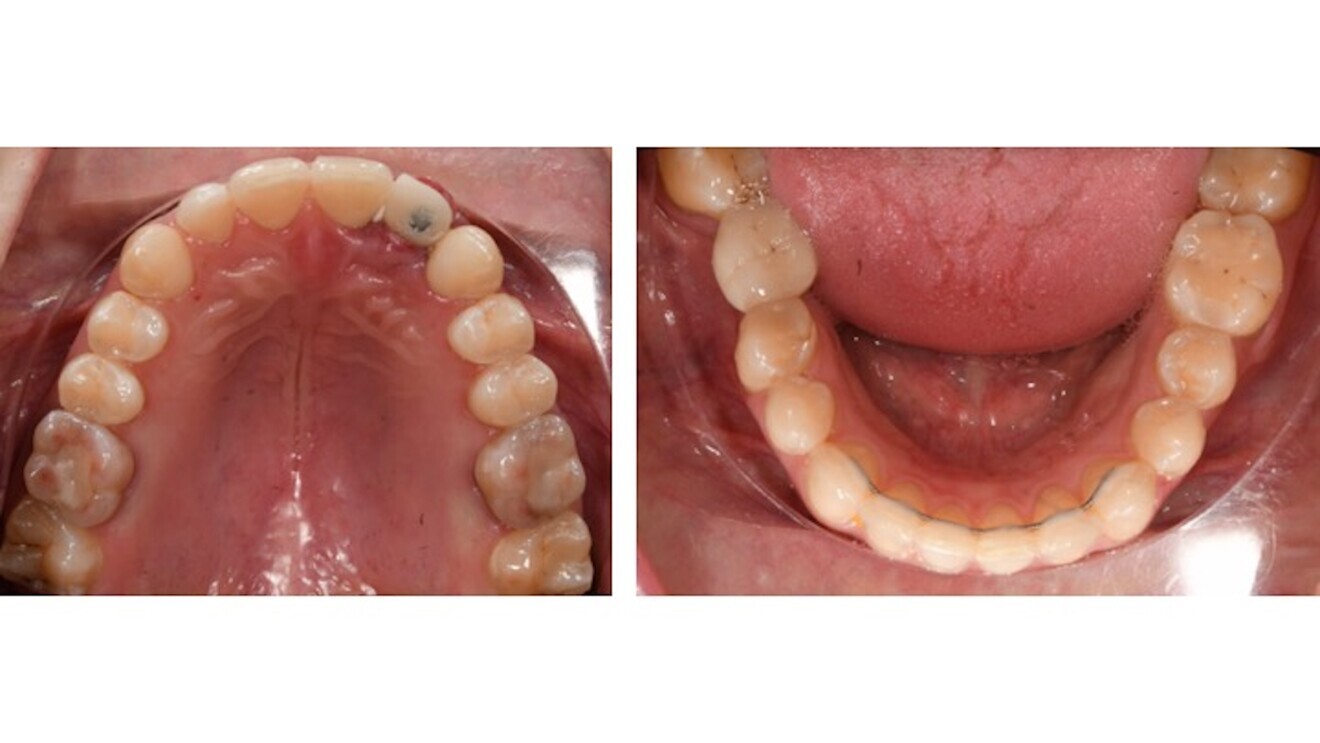

Figs. 11a & b: Occlusal photographs after orthodontic treatment.